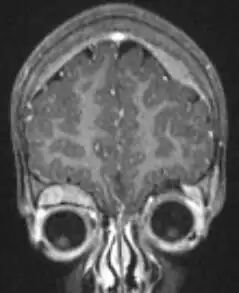

Microscopische opname van een typisch neuroblastoom met rosette formatie. | ||||

Microscopisch beeld

Onder de microscoop zijn de tumorcellen klein, rond en blauw, en vormen een rosettepatroon. Ook pseudorosetten zijn beschreven, waarbij de tumorcellen niet rond een bloedvat maar rondom een uitloper van een zenuwcel (een neutropil) zijn gegroepeerd. Het neuroblastoom is een van de perifere neuroblastische tumoren (pNT) en heeft eenzelfde soort oorsprong en heeft een breed patroon van differentiatie (uitgroeien tot een bepaald soort cel) variërend van goedaardig .ganglioneuroom via een stromarijk ganglioneuroblastoom met een mengsel van neuroblastoom-cellen in groepjes, tot een zeer kwaadaardig neuroblastoom. Dit onderscheid is samen met de leeftijd en de mitose-karyorhexis (kapot gaan van de celkern)-verhouding een belangrijk middel te bepalen of de vooruitzichten "gunstig " of "ongunstig " zijn. In 1999 is hier een indeling voor gemaakt, die in 2003 is herzien.[18]